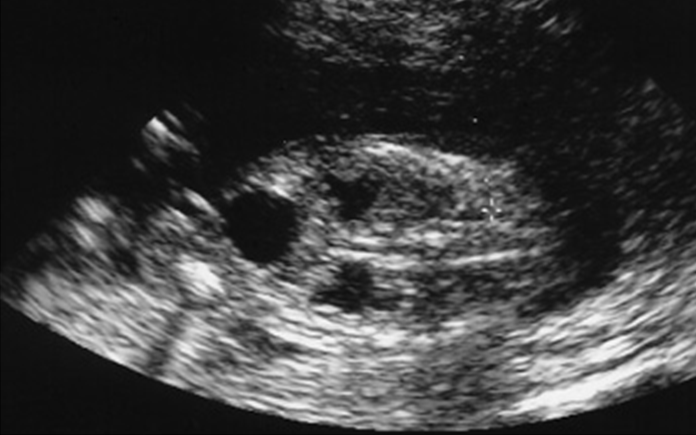

hydronephrosis